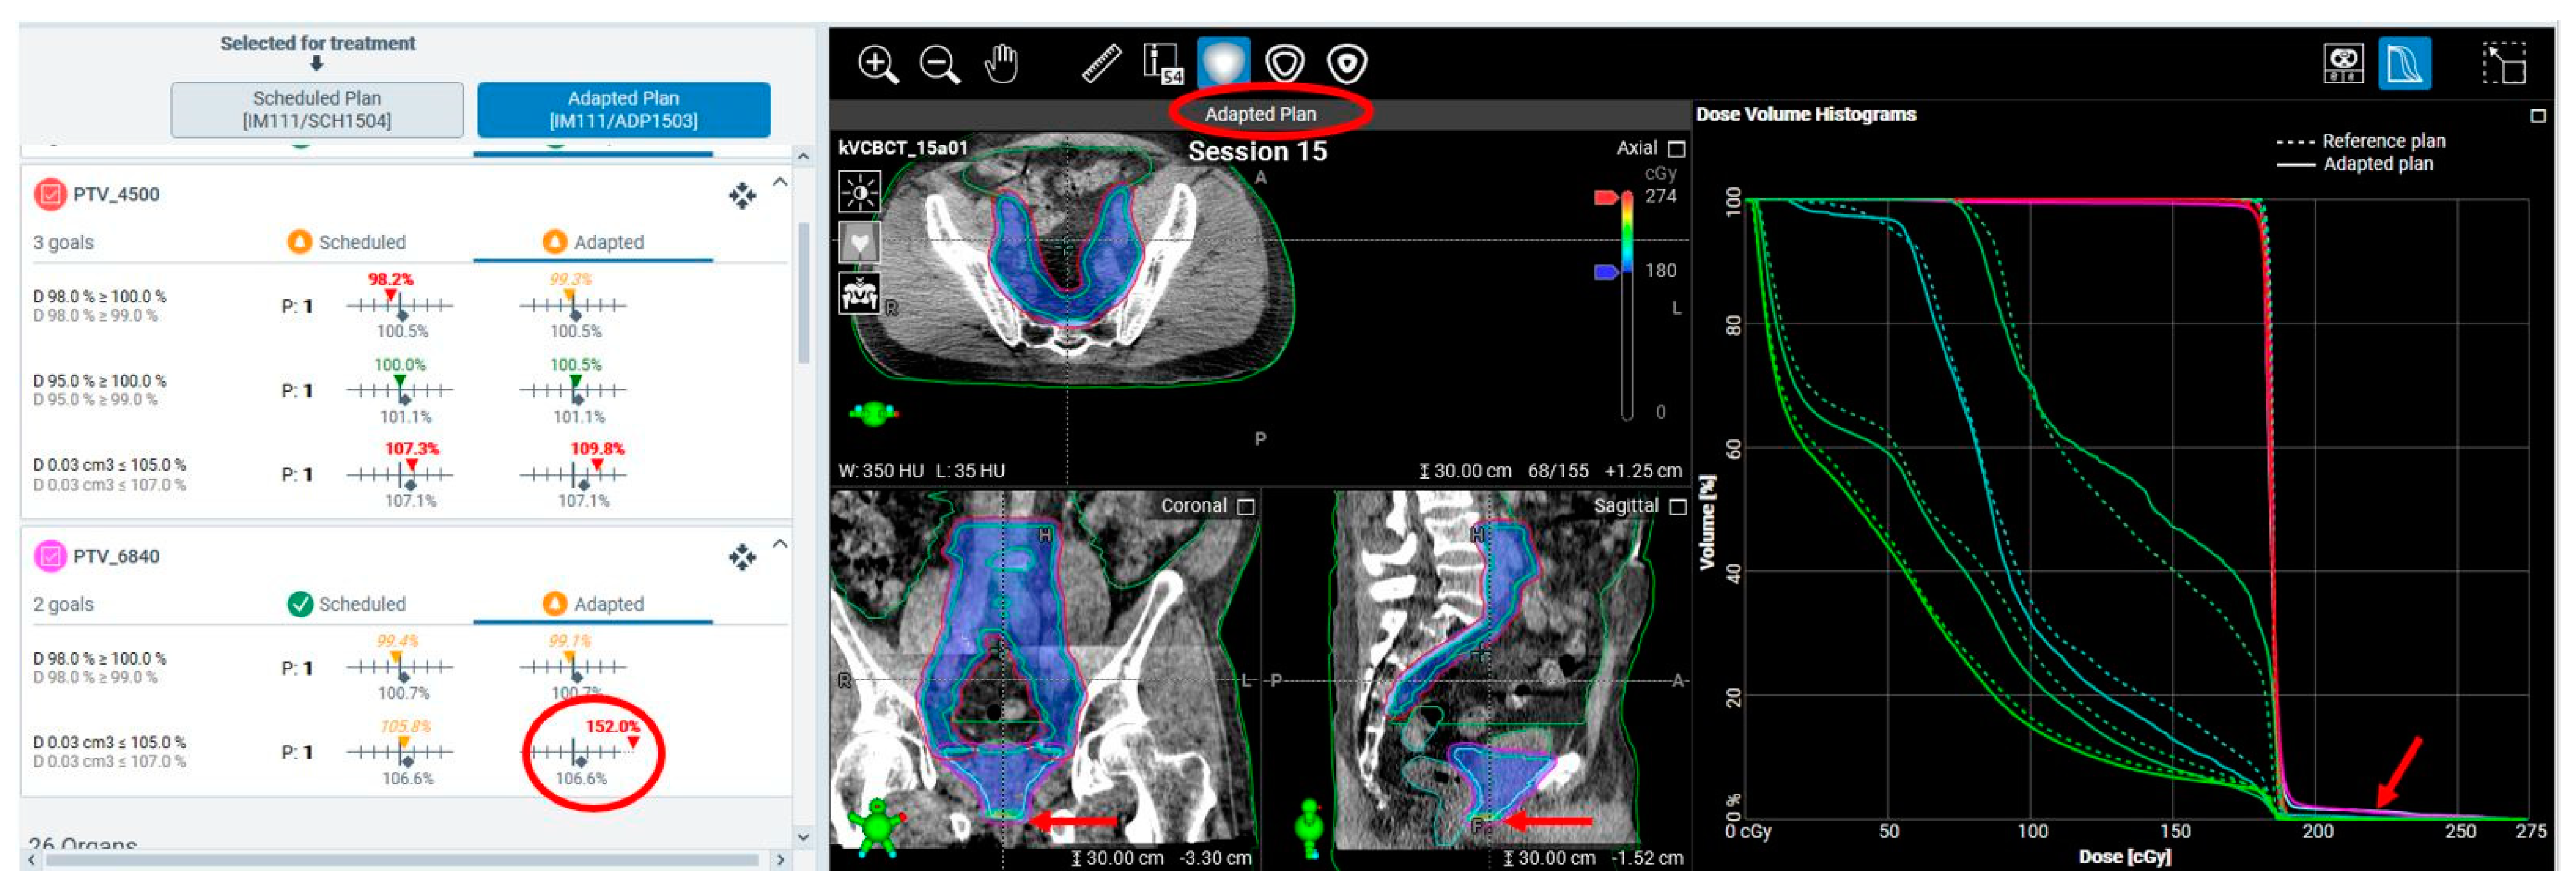

3.2.3. Treatment Planning and Execution Failures

| Unacceptable hotspots in adaptive plans due to planning system variability | 10% estimated, not quantified | 5% estimated, not quantified | |